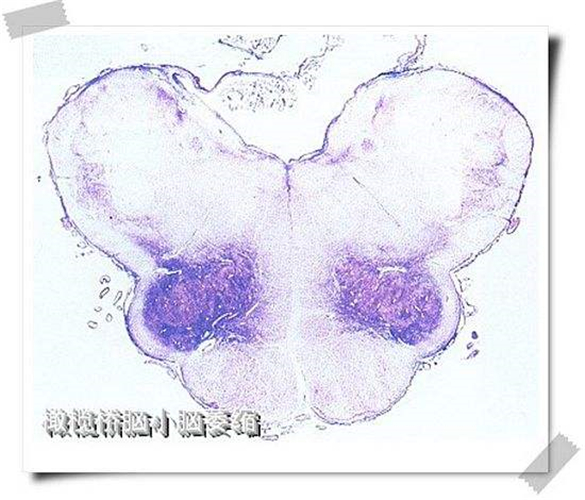

橄欖橋腦小腦腦萎縮標本